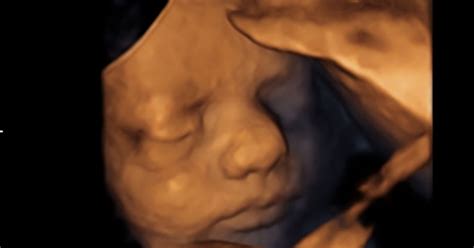

- Zgodnji razpok mehurja: Če se amnijska vrečka, ki vsebuje plodovnico, prezgodaj razpoči ali je plodovnice premalo, lahko medenične kosti matere pritiskajo na otrokovo glavico, kar povzroči otekanje. To stanje lahko zdravniki opazijo že med ultrazvočnim pregledom pred porodom.